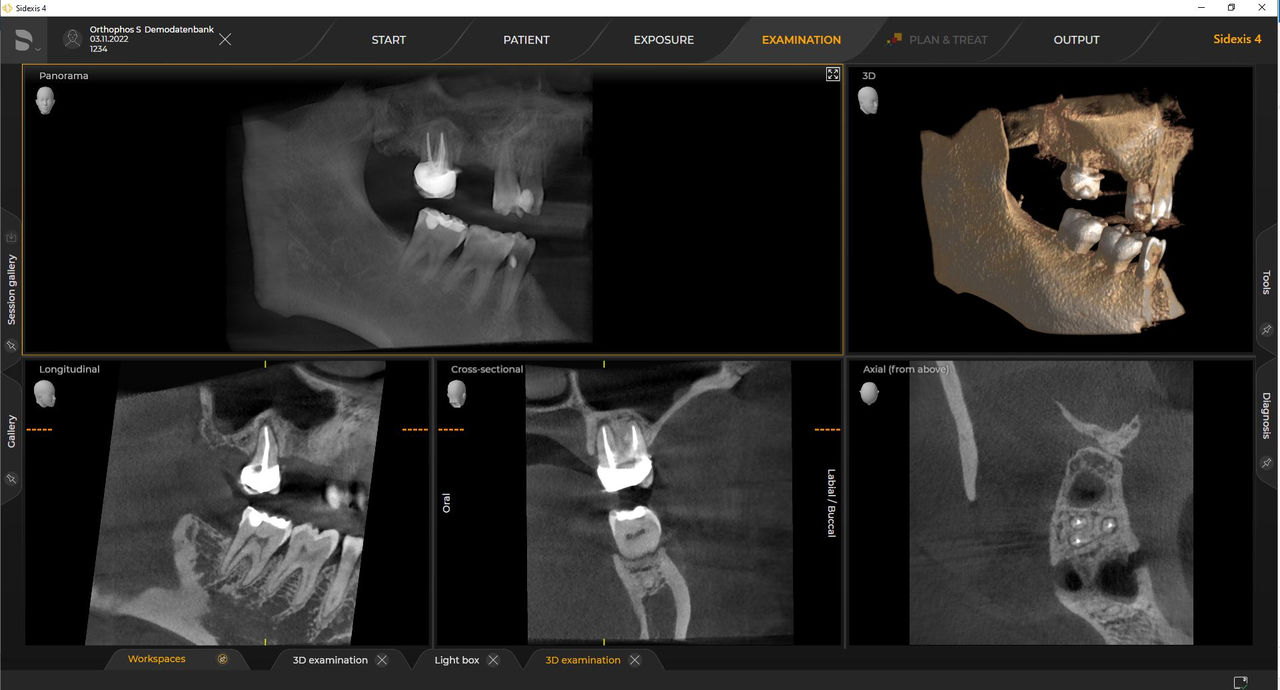

Con el modo de dosis baja inteligente 3D, obtiene imágenes 3D en el rango de dosis de una imagen radiológica 2D. En el modo HD (hasta 1400), las imágenes individuales se obtienen durante una única rotación y se convierten en un volumen 3D con hasta 80 μm para imágenes de bajo ruido en alta resolución.

Las unidades de radiología de Dentsply Sirona funcionan exclusivamente con Sidexis 4. Sin embargo, la migración de datos de Sidexis XG a Sidexis 4 es muy fácil. Sidexis 4 permite una experiencia digital completa con las últimas herramientas